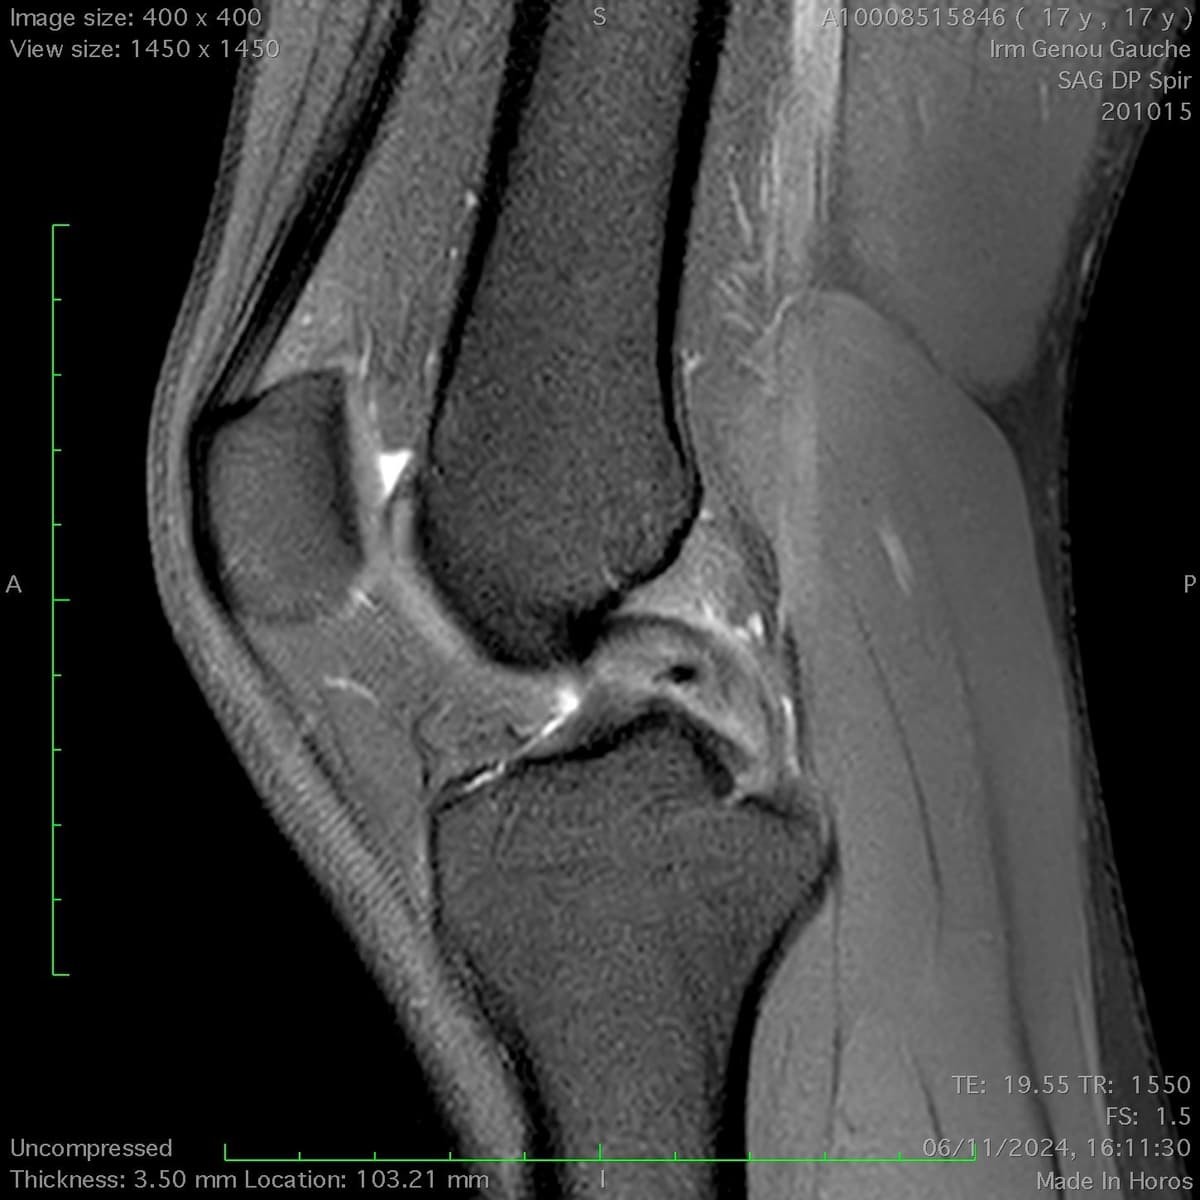

Rupture partielle du ligament croisé postérieur

Rupture partielle du ligament croisé postérieur chez un joueur de rugby